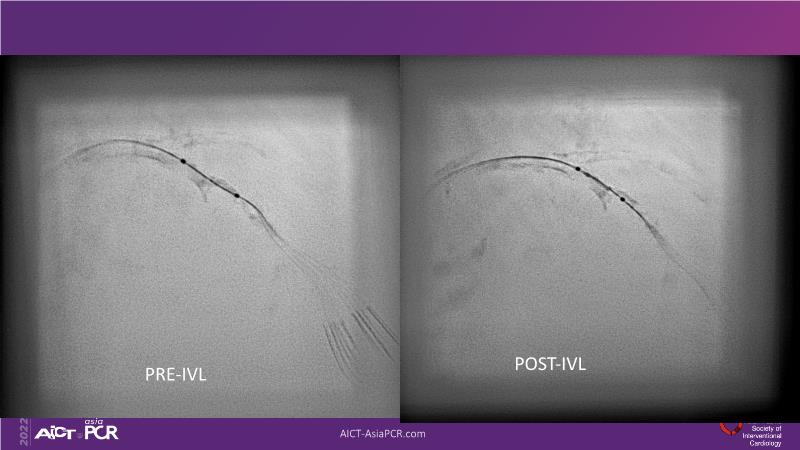

With this session, keep up to date on the evidence, trials and outcome data for intravascular lithotripsy in severely calcified lesions. Learn how to use this technique in real-world patients and understand its role in the treatment algorithm for severely calcified coronary lesions.

- To learn how to use intravascular lithotripsy in real-world patients with severely calcified coronary lesions